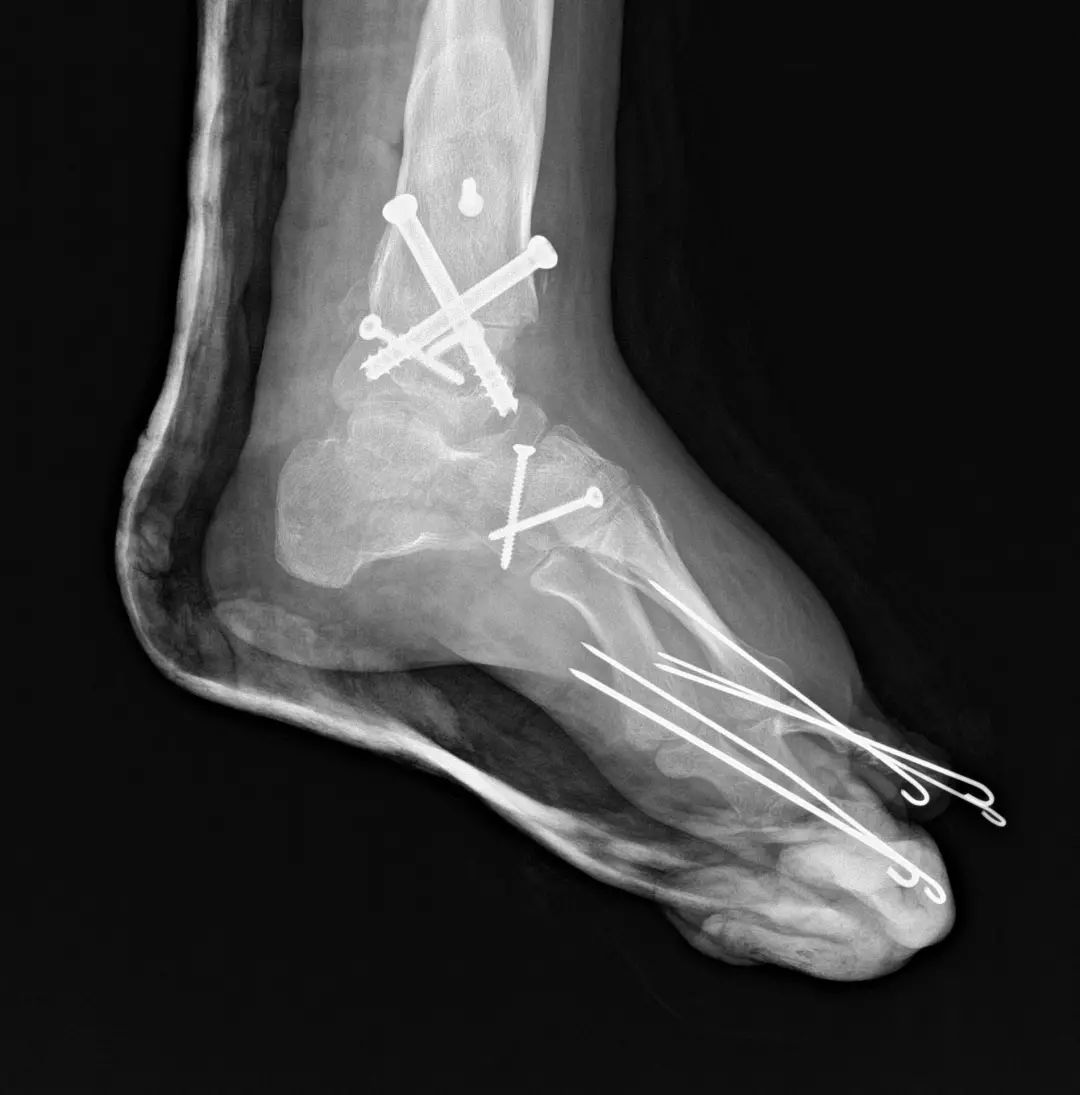

根据患者的病情,同济大学附属同济医院足踝外科团队讨论后,最终确定了左足踝关节融合、内侧楔骨Cotton截骨;右足第一跖骨抬高的手术方案,由俞光荣教授主刀,患者术后恢复状况良好,她扭曲的足终于可以完全放平了。医保报销后,这次复杂的矫形手术只花费了7千多元,远远低于患者及其家属的预期,对此小王表示非常感谢和满意。

图:术后扁平足足畸形是指足部形态或结构的异常,包括先天性足畸形和后天性足畸形,烧伤、急性创伤、长期穿高跟鞋或不合适的鞋子都可能导致足部的后天性畸形。足部畸形影响足的站立和负重,影响步态,外观不美观,穿鞋也不方便,对生活带来很大困扰。同济大学附属同济医院足踝外科早在上世纪90年代就开展了足部畸形矫正手术,积累了丰富的手术经验,是国内最早涉及足部矫形的团队之一,秉承“最小的创伤,最简单的方法,最低的医疗成本,获得最好的疗效”这一理念,一心一意为病人解决难题。